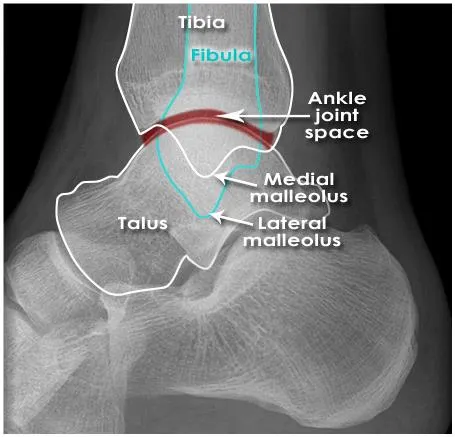

C. Lateral X-ray

Ankle bone and lig. anatomy

Not visible

Joint space

understanding of the anatomical position of ligaments is required to appreciate the presence of ligament injuries

Ankle anatomy (Lig.)

Syndesmotic ligament complex

Axial, rotational, & translational stability

Deltoid (medial) ligament complex

Lateral (fibular collateral) ligament complex